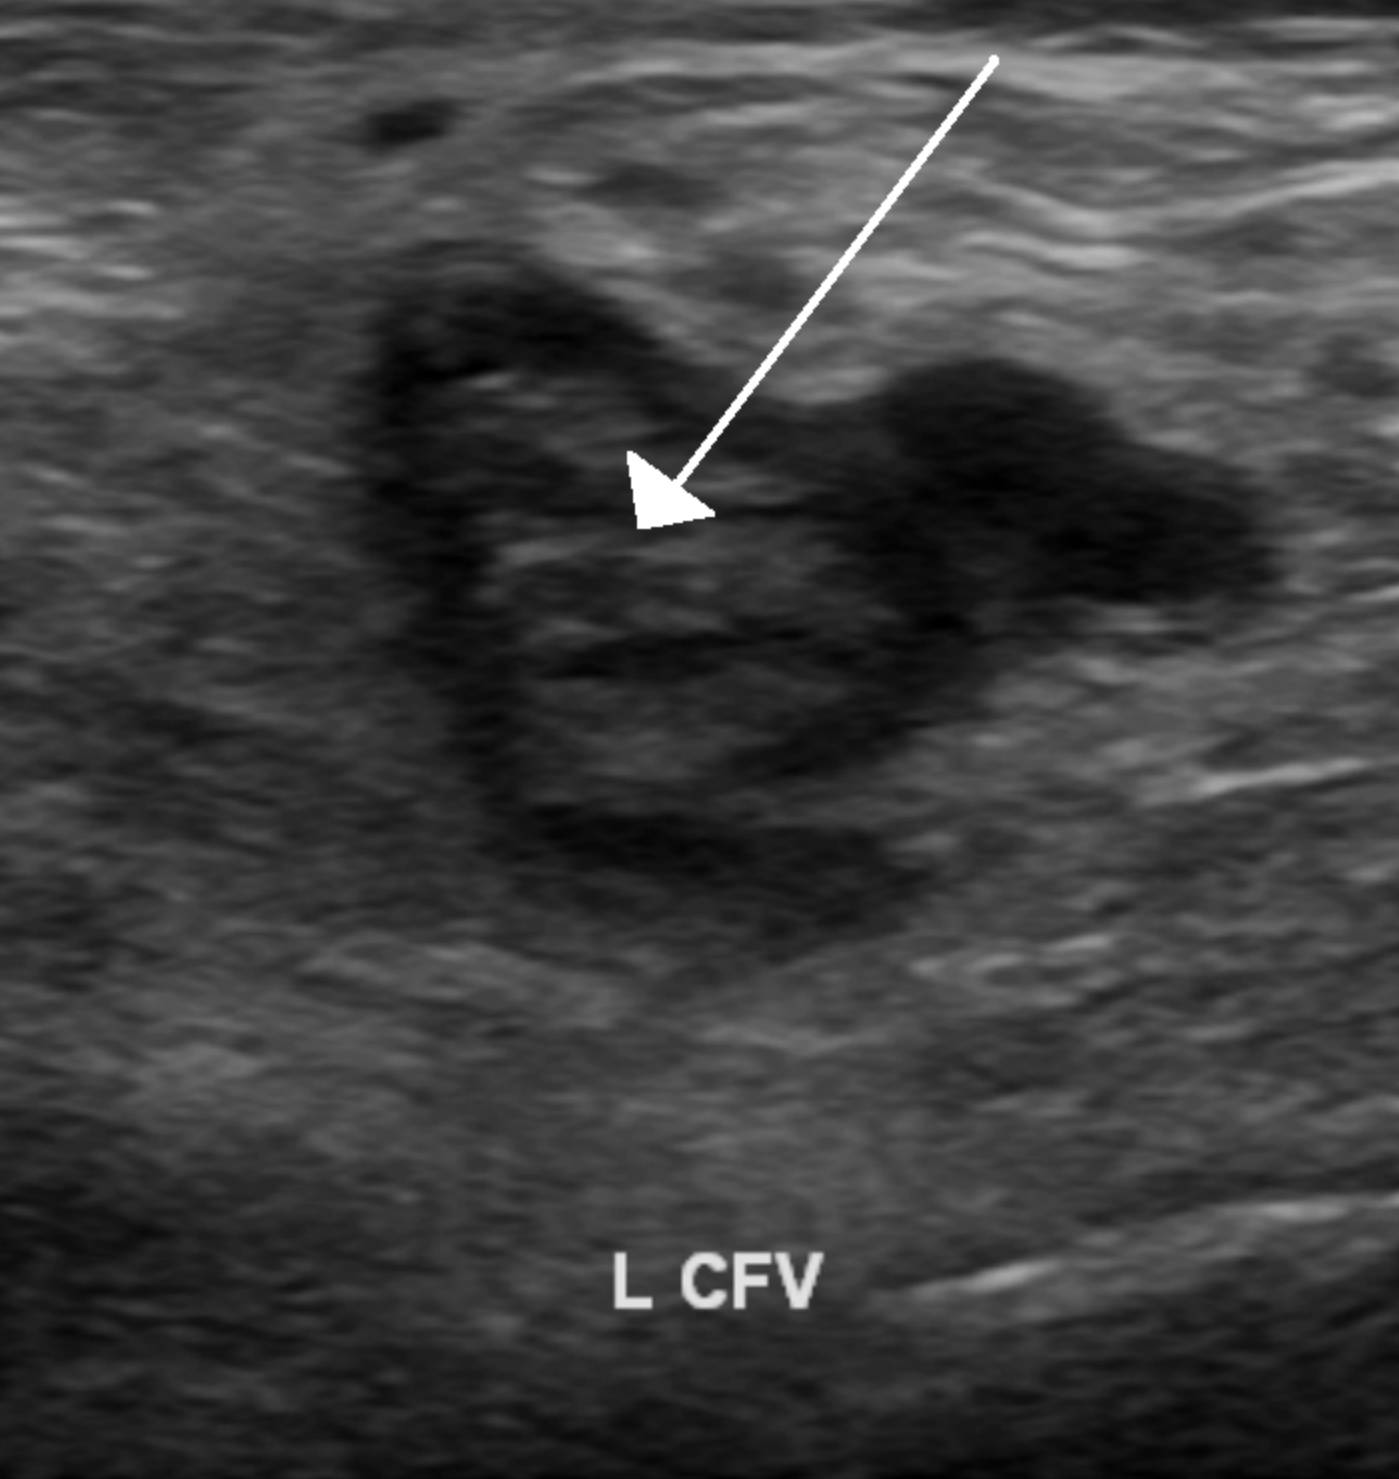

White Arrow (Thrombus): The white arrow points to an intraluminal mass that appears heterogeneous and echogenic (brighter than the surrounding fluid). This structure is the blood clot itself, which occupies the vessel lumen and prevents the normal flow of blood, a hallmark sign of thrombosis on an ultrasound.

L CFV (Left Common Femoral Vein): This label identifies the specific anatomical location of the image, the left common femoral vein. This is a major deep vein in the upper thigh that is formed by the confluence of the femoral vein and the deep femoral vein, serving as a critical pathway for venous return from the lower extremity to the heart.

Deep Vein Thrombosis (DVT) is a serious medical condition characterized by the formation of a blood clot (thrombus) within a deep vein, most commonly in the lower leg, thigh, or pelvis. The image provided illustrates a classic presentation of DVT in the common femoral vein. Under normal physiological conditions, veins on an ultrasound appear as anechoic (black) fluid-filled structures that are easily compressible. However, when a clot is present, the vein typically expands, becomes non-compressible, and contains visible internal echoes, as seen in the labeled scan.

The location of the clot in the common femoral vein is particularly significant clinically. Proximal clots (those in the popliteal vein and above, including the femoral and iliac veins) carry a much higher risk of breaking loose and traveling to the lungs than distal clots in the calf. Therefore, identifying a blockage in the L CFV requires immediate medical intervention to stabilize the clot.

The ultrasound image of the left common femoral vein provides a definitive view of a pathological thrombus. Recognizing the echogenic appearance of the clot within the vessel lumen allows healthcare providers to diagnose deep vein thrombosis accurately and initiate life-saving treatment. By understanding the anatomy of the femoral veins and the risks associated with venous thromboembolism, medical professionals can effectively manage patients to prevent fatal complications like pulmonary embolism.